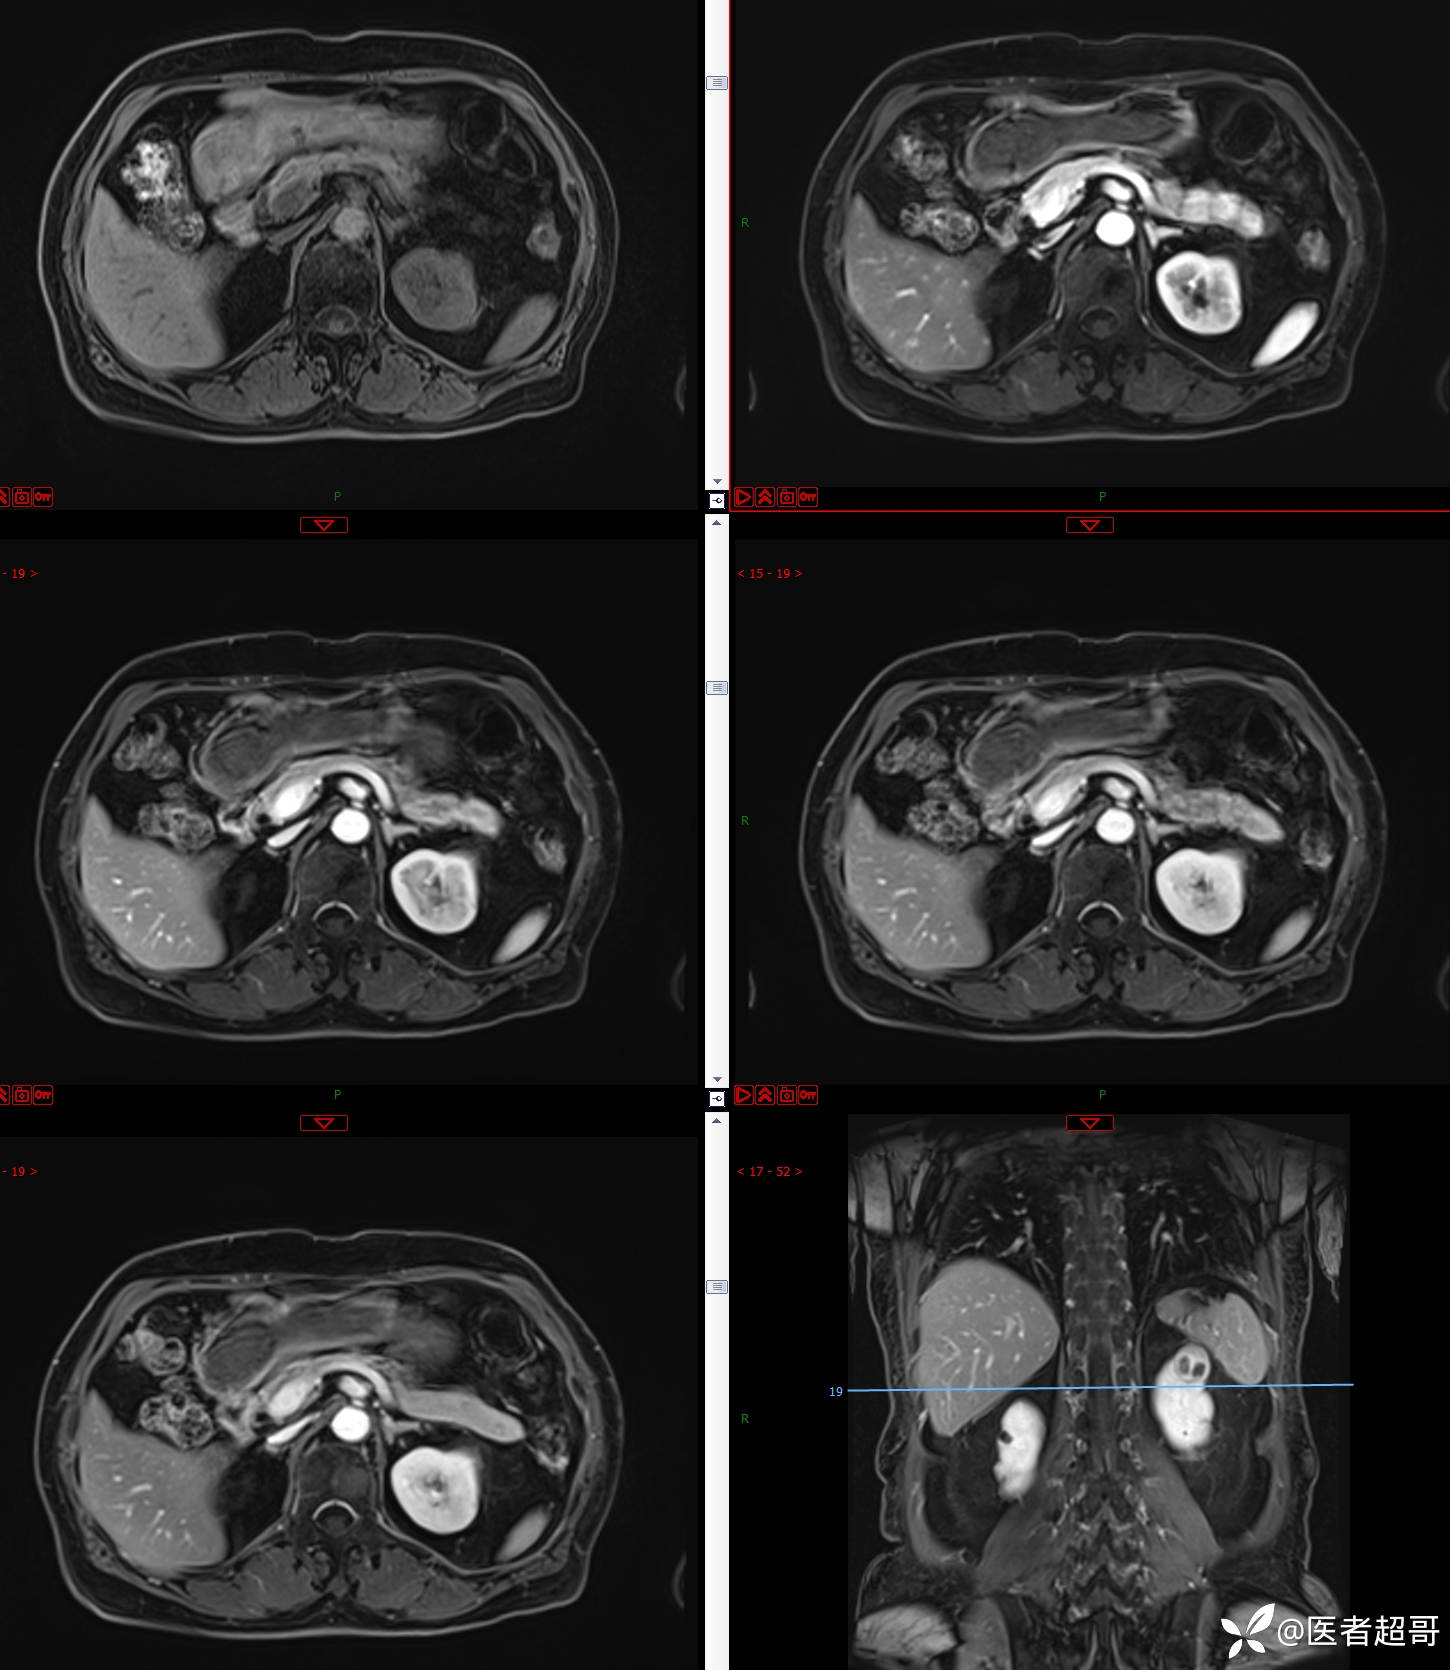

左肾占位2个月就诊,有病理,请分析!

主 诉:查体发现左肾占位2月。

现病史:患者自述2月前于镇中心卫生院行腹部超声发现:左肾实性占位。患者无尿频尿急尿痛,无发热寒战,无恶心呕吐。未行特殊治疗。现患者为求进一步诊治,就诊我院,门诊以“肾肿物”为诊断收入院,患者自发病以来,神志清,精神可,饮食可,睡眠一般,大便正常,体重未见明显改变。